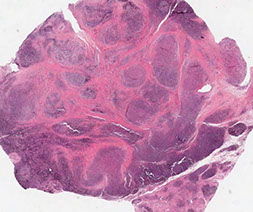

Polyarteritis Nodosa

PolyArteritis Nodosa (PAN)

Immune complex-mediated transmural vasculitis c fibrinoid necrosis of small and medium muscular arteries

- not present in arterioles, capillaries or venules

- lungs are spared

Sx: abd pain, myalgia, HTN, neurologic dysfunction, cutaneous eruptions

- involves renal vessels, nerves (monomeuritis multiplex), skin and visceral (kidneys, mesentery) vessels, though not pulmonary arteries (lungs are spared)

*** PAN = Pulmonary Arteries Normal ***

- lesions are different ages

Micro: bx shows segmental fibrinoid necrosis of inflamed arterial walls, c a predilection for branch points

- characteristic feature is segmental nature of involvement, c active and healing lesions next to normal segments of bv's

Labs: 30% have hep B seropositivity

- multiple aneurysms and constrictions on arteriogram

- No assoc c ANCAs

Tx: corticosteroids, cyclophosphamide

- same tx as Wegener's; cures 90%; fatal if untx'd